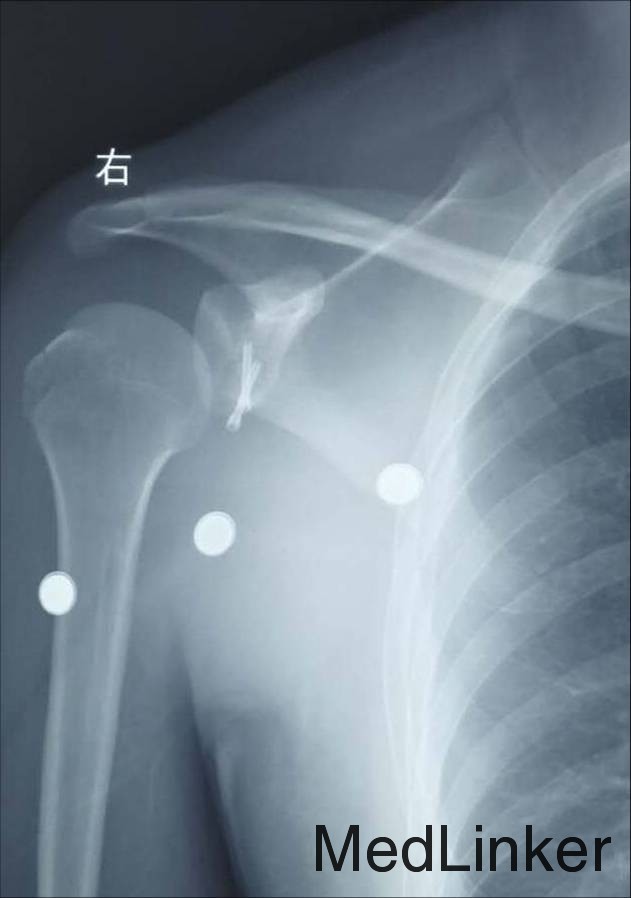

患者谢某某,男性,28岁,已婚 患者坠马后摔伤右肩部,局部肿痛伴活动受限7日 外院就诊摄片示:右肩胛骨折;右肱骨大结节骨折 右上肢外展支架外固定

右肩甲盂骨折